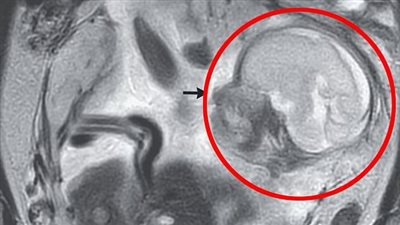

وبعد تشخيص حالة السيدة اكتشف الأطباء أنها أصيبت بظاهرة طبية نادرة من نوعها تحدث لنساء فوق الـ40، وتسمى بـ الجبيرة العشرية، وتعبر هذه الظاهرة عن فقدان المرأة لبطانة الرحم بأكملها مرة واحدة بشكل مفاجئ بدلًا من تجزئة هذا النشاط على عدة أيام بشكل طبيعي.

فقدان بطانة الرحم بالكامل

وحسب ما نشر فإن في فترة الحيض العادية، تتكاثف جدران الرحم لإعداد جسم المرأة للحمل، لتأهيل عنق الرحم وتجهيزه بشكل طبيعي، وعندما لا يحدث حمل يتخلص الجسم من تلك الجدران السميكة على مدار ثلاثة إلى سبعة أيام، مما يؤدي إلى النزيف الدموي، وهذا ما تعنيه فترة الدورة الشهرية.